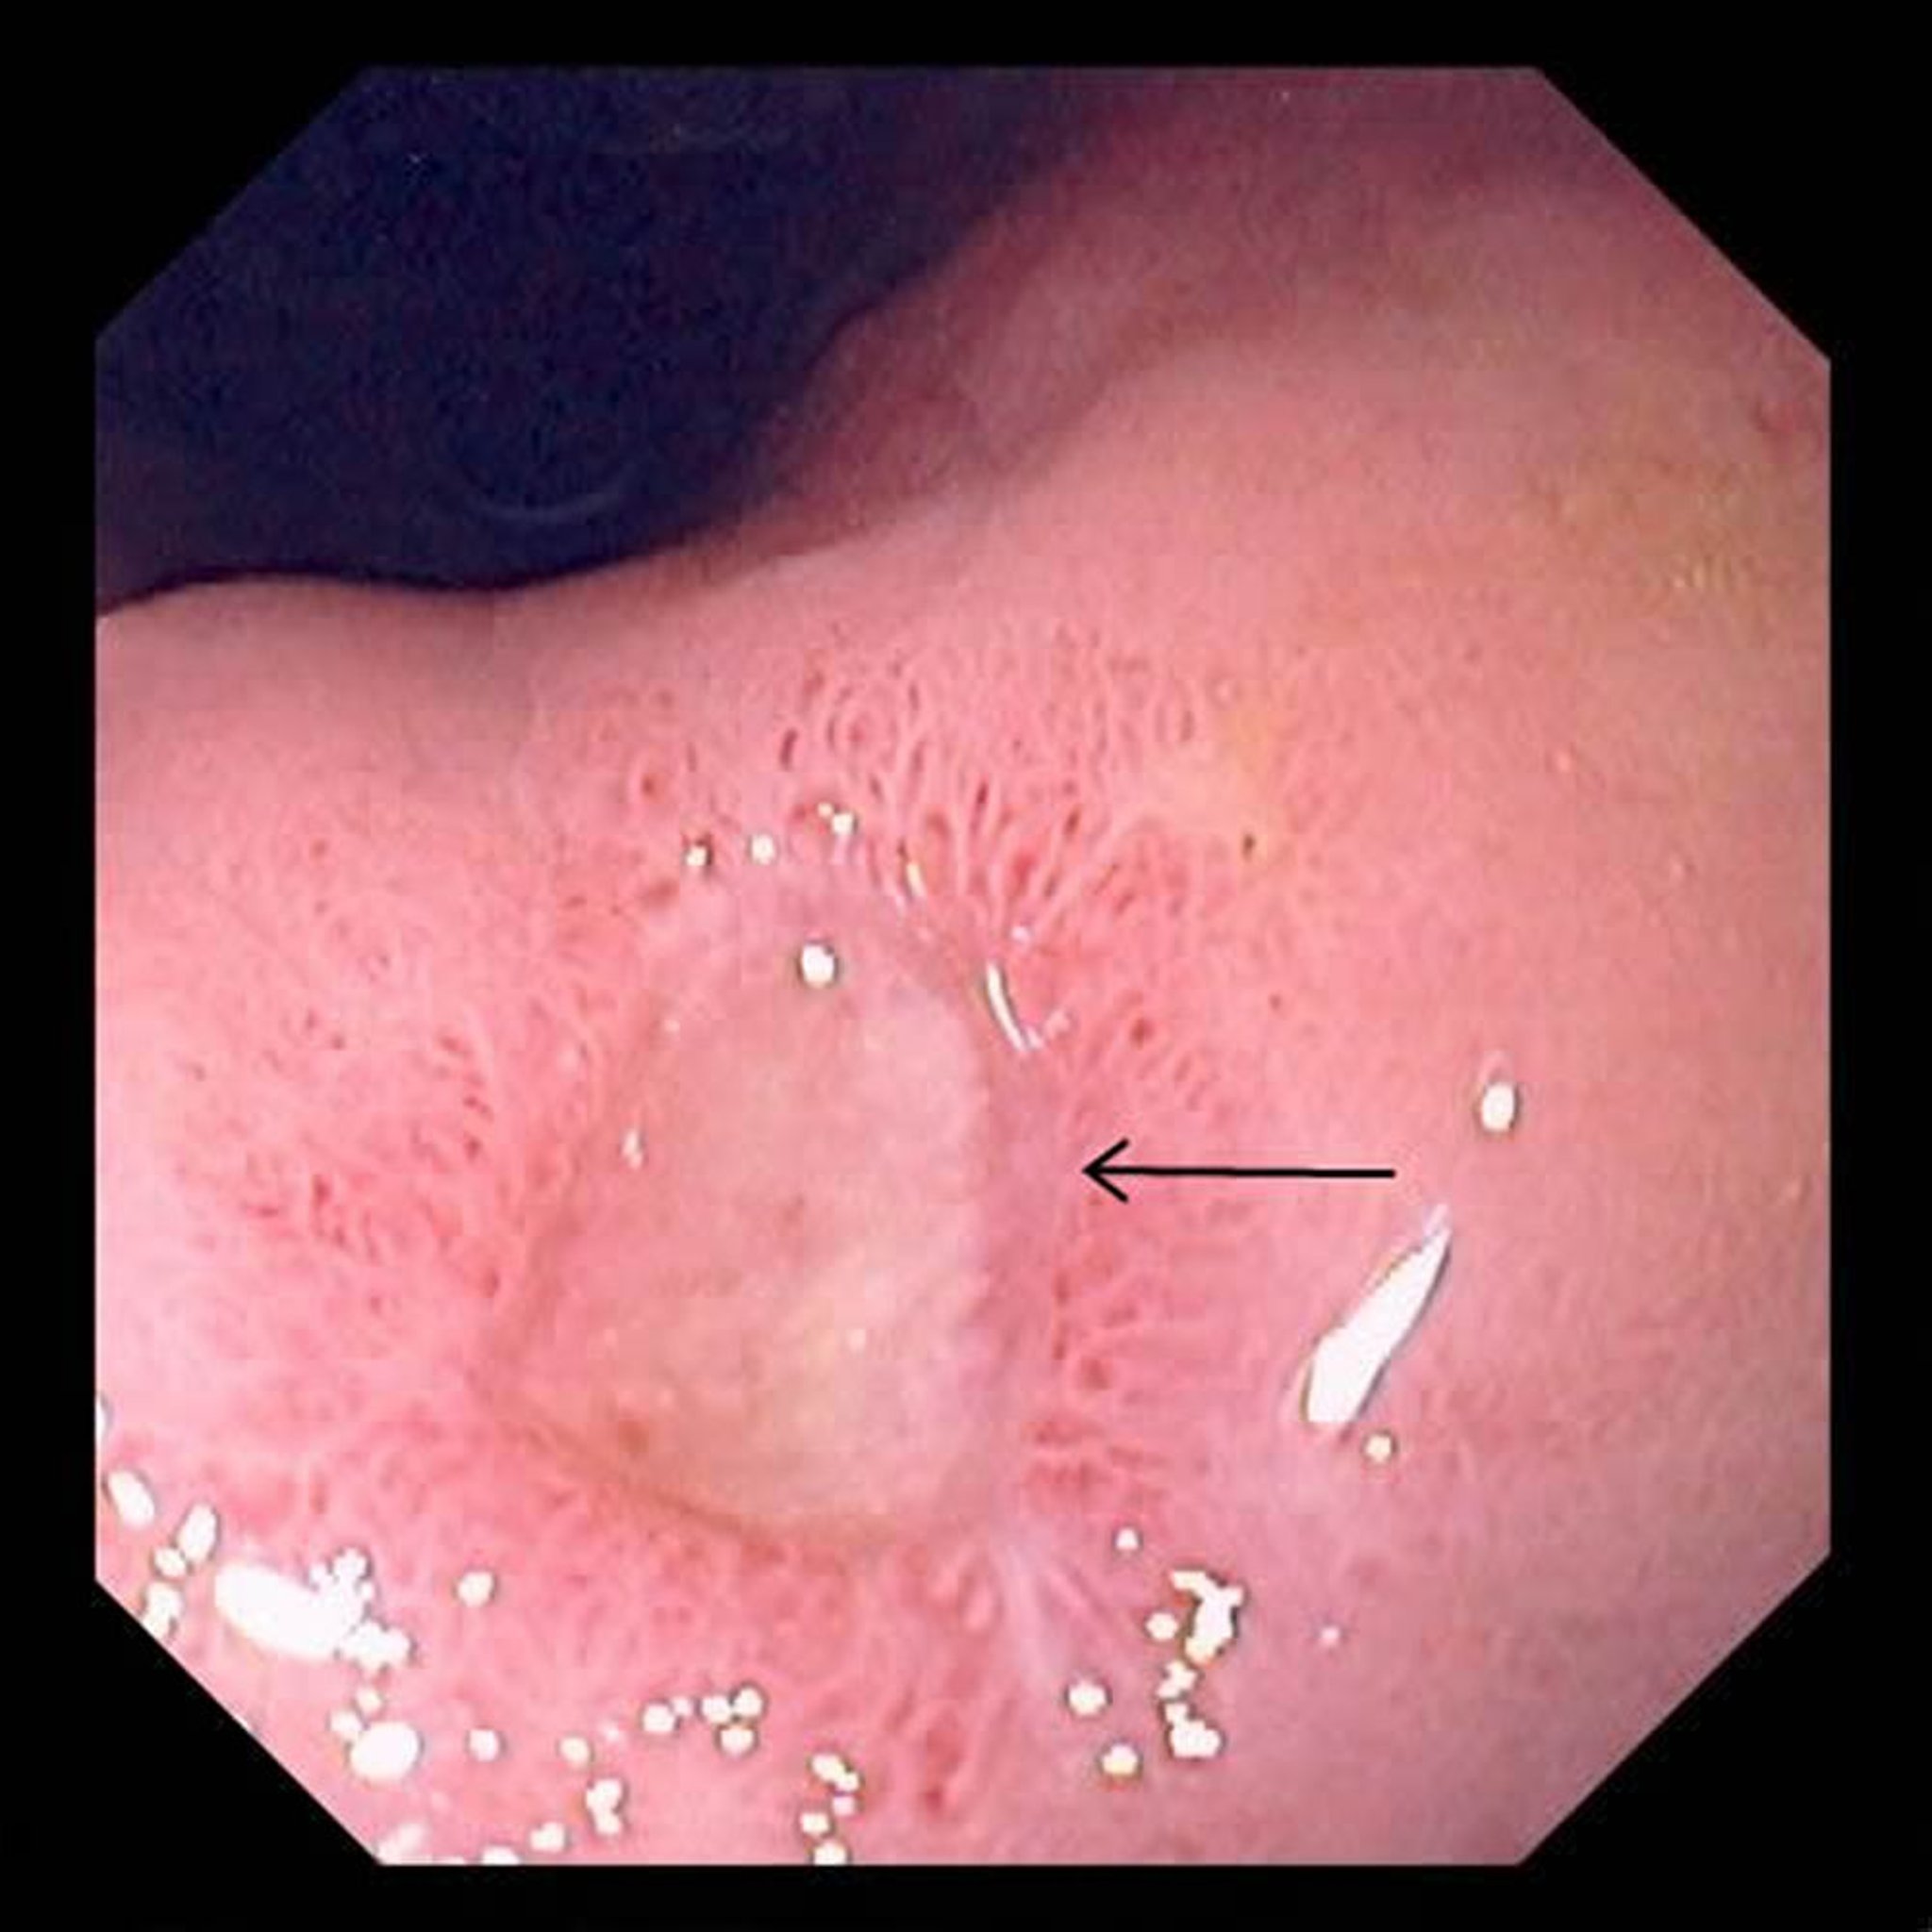

Esta foto muestra una úlcera de gran tamaño (flecha) en el estómago.

Foto proporcionada por David M. Martin, MD.